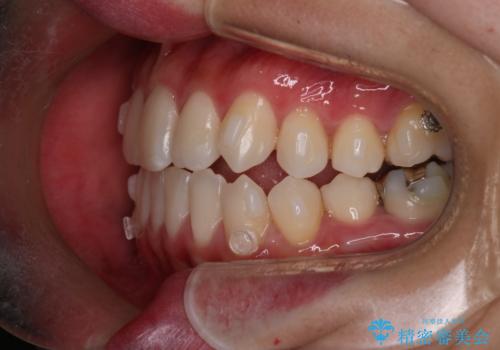

【インビザライン】歯の本数少ないのにがたつきがある セラミックインレー

- 右上2番が欠損しており、歯並びをバランスよくしたいということで来院されました。

右上2番が欠損しているため、見た目と噛み合わせの両方のバランスを整えるために経過を追いながら必要な部位にゴム掛けをしました。

また矯正後、患者様の希望で

メタルインレーをセラミックインレーにやりかえさせていただき、さらに綺麗に仕上がりました。